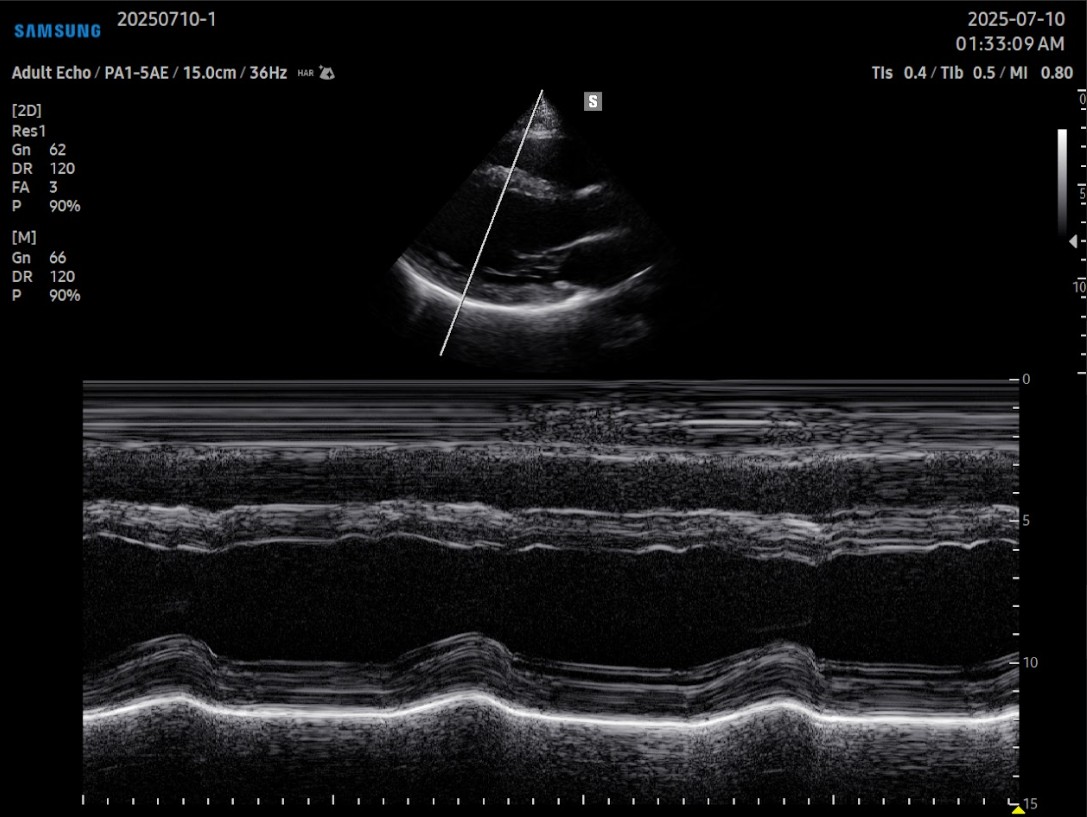

Gracias a su arquitectura Crystal™ (CrystalBeam™ y CrystalLive™), el cV6 entrega imágenes 2D y Doppler con gran claridad y resolución, lo que permite visualizar estructuras vasculares finas, flujos lentos y movimiento miocárdico con un nivel de detalle excepcional.Tecnologías como MV-Flow™, LumiFlow™, ClearVision y S-Flow™ optimizan la detección de microvasculatura y realzan el contraste sin sacrificar velocidad, siendo especialmente útiles en estudios cardiacos, vasculares y pediátricos.

En el ámbito cardiológico, el V6 incorpora herramientas avanzadas como HeartAssist™, que reconoce automáticamente las principales vistas cardíacas y facilita la orientación del operador. También incluye Strain+™, AutoEF™, StressEcho, y ArterialAnalysis™, que permiten evaluar la deformación ventricular, la fracción de eyección y la rigidez arterial de forma automatizada, estandarizando los resultados entre operadores y reduciendo los tiempos de exploración.